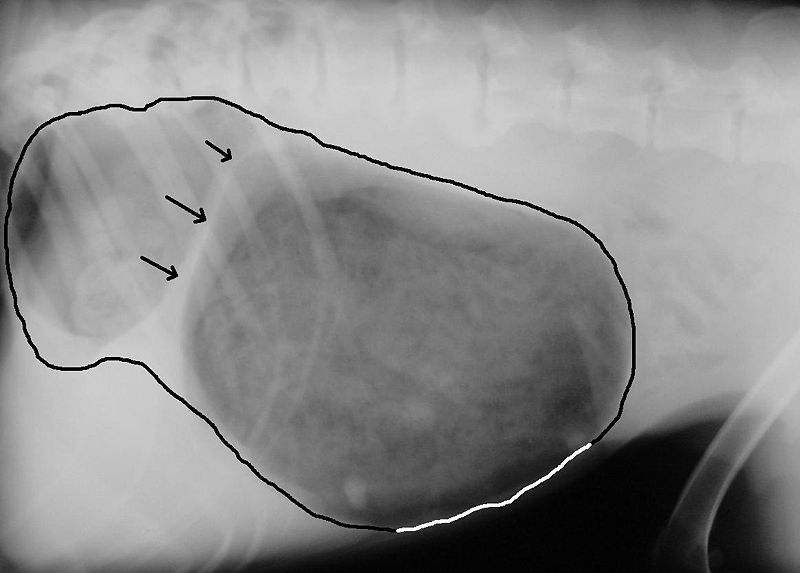

Canine idiopathische Lungenfibrose

Die canine idiopathische Lungenfibrose ist eine Erkrankung des Zwischengewebes (Interstitium) der Lunge, die ohne erkennbare Ursache (idopathisch) entsteht. Sie tritt vor allem bei mittelalten und alten Tieren und gehäuft bei einigen Terrierrassen wie z.B. West Highland White Terrier, Staffordshire Bullterrier, Scottish Terrier auf. Sie entspricht in der Pathologie der kryptogenen organisierenden Pneumonie des Menschen.

Klinisch äußert sich die Erkrankung in einer fortschreitenden Atemnot, die vor allem bei der Einatmung auftritt. Die Atemfrequenz ist erhöht (Tachypnoe), es kommt zu Blauverfärbungen der Schleimhaut (Zyanose) und der Bewegungstrieb vermindert sich zunehmend. Im fortgeschrittenen Stadium ist die Atemnot schon in Ruhe ausgeprägt und der Hund atmet mit weit geöffnetem Maul. Husten ist vor allem in der Frühphase der Erkrankung häufig. Bei übergewichtigen Tieren sind die Symptome verstärkt. Sekundär kann es zu einem Lungenhochdruck (pulmonale Hypertonie) und zu einer Verdickung der rechten Herzkammer (Rechtsherzhypertrophie) kommen.

Beim Abhören der Lunge (Auskultation) sind deutliche Knistergeräusche zu hören. Im Röntgenbild zeigt sich eine Verdichtung des Lungengewebes mit deutlich hervortretender Zeichnung der Bronchien. Die Lunge erscheint verkleinert, die Luftröhre erweitert.

Die Diagnose ist klinisch nur als Verdacht zu stellen. Die hochauflösende Computertomografie (High Resolution CT) kann die Erkrankung mit hoher Sicherheit feststellen, ist aber in der Tiermedizin kaum verfügbar. Eine Sicherung kann daher nur mit einer Lungenbiopsie und anschließender pathologischer Untersuchung erfolgen, wobei die Lungenbiopsie nicht ohne Risiko ist.